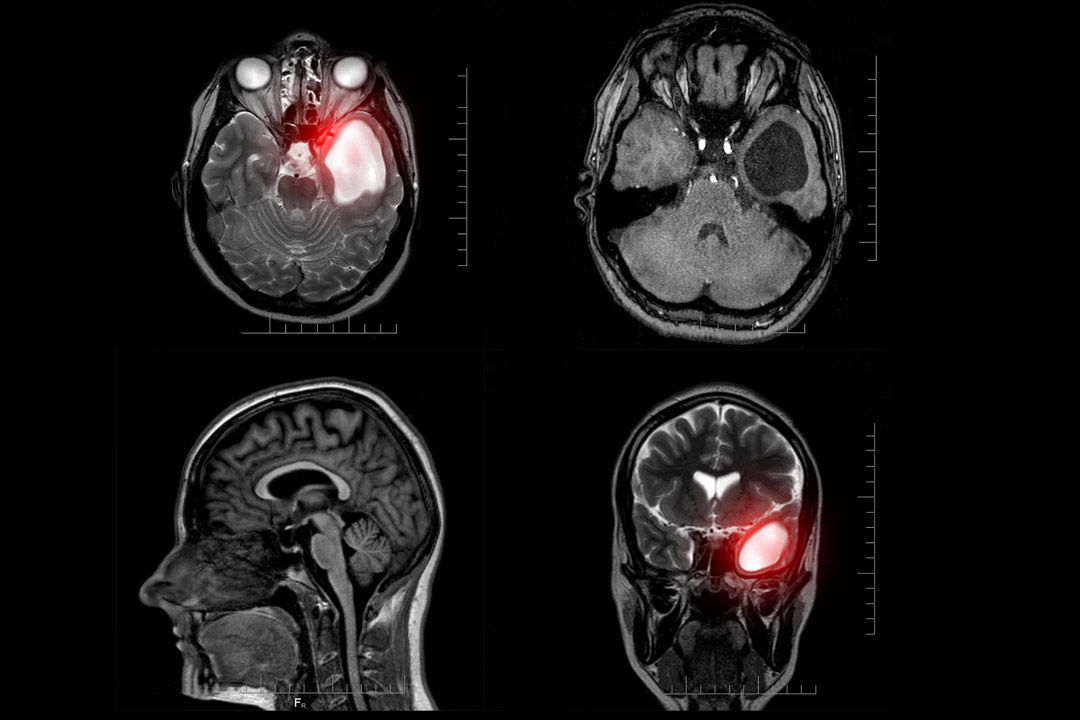

Киста В Голове Фото

Киста В Голове Фото 146 фотографий